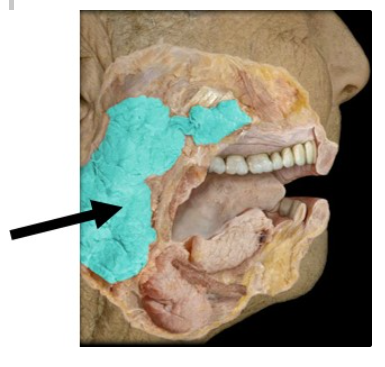

What gland is indicated in the figure?

Parotid gland

The structure indicated in the image secretes a watery solution containing an enzyme that breaks down __________ in response to __________ stimulation.

carbohydrates; parasympathetic